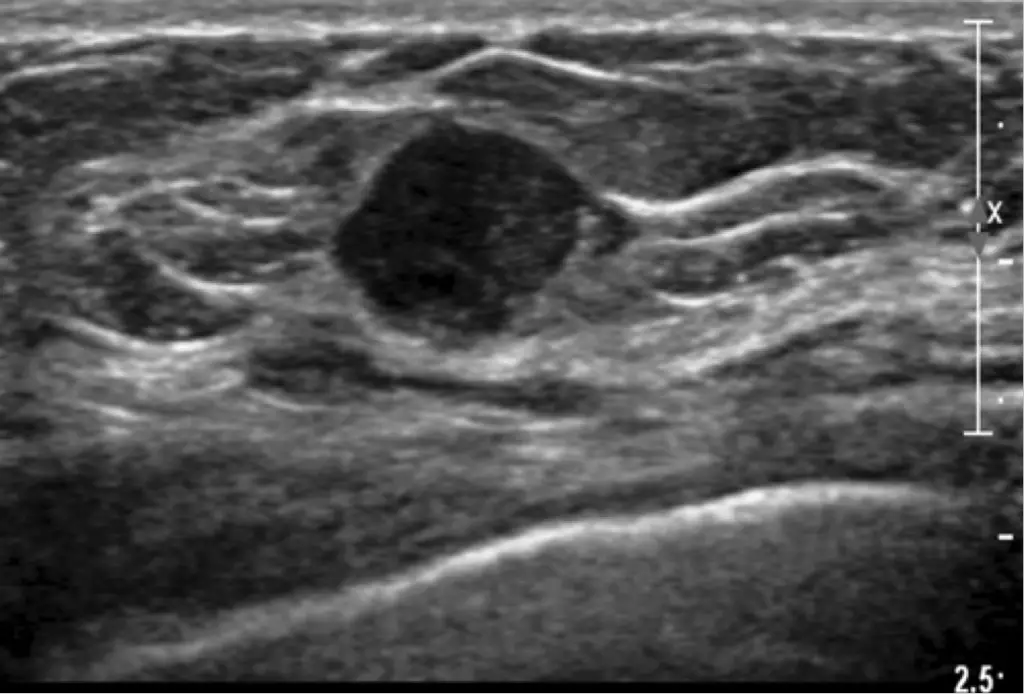

Quando il segnale circoscrive una zona ben specifica e focalizzata, quindi caratterizzata da una formazione rotonda, si attribuisce alla zona il nome di nodulo ipoecogeno. Il nodulo in questione avrà importanza rilevante all’interno di questo articolo, perché è tra le manifestazioni cliniche più conosciute. Stando ali ultimi studi, il termine ipoecogeno a quella parte di tessuto che produce una minore densità o che presenta meno brillantezza rispetto al resto. Un nodulo si dice ipoecogeno quando le zone d’ombra al momento della diagnosi ecografica sono sinonimo della presenza di liquido. Tranquilli, non costituisce una patologia cancerosa pericolosa. Dove è possibile ritrovarli? Un nodulo ipoecogeno, come detto in precedenza, lo si può riscontrare in molti organi e tessuti del corpo.

Cosa succede in questi casi? Il rilevatore non è in grado di visualizzare il segnale in modo da rendere visibile quella zona all’’operatore. Perciò apparirà nera, quasi come se l’ecografo avesse dimenticato di riprodurre quella zona. Capite bene che un’esame del genere ha un buon valore diagnostico poiché, tramite questo esame, è possibile, in modo del tutto non invasivo analizzare molte caratteristiche dell’organo interessato.